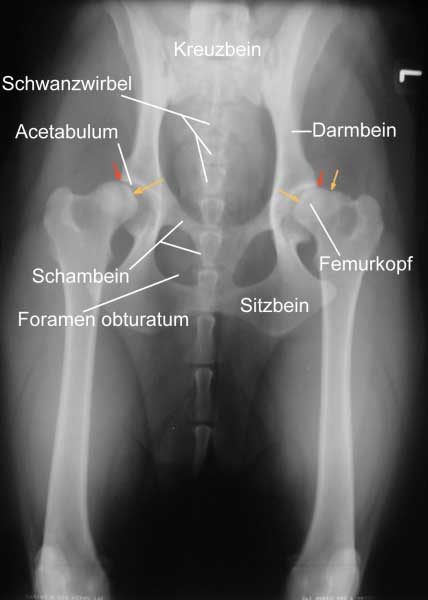

Eine zuverlässige Möglichkeit zum Erkennen des Schweregrades der Erkrankung bildet die Röntgenuntersuchung. Da bei dieser die Gelenke überstreckt werden müssen, was beim Vorliegen einer HD starke Schmerzen verursacht, wird sie unter einer Kurznarkose durchgeführt. Voraussetzung für eine aussagekräftige Diagnose ist die exakte Positionierung des untersuchten Tieres in Rückenlage mit gestreckten, parallel gelagerten Oberschenkeln und orthograd zum Strahlengang eingedrehten Kniescheiben.

Zusätzliche Aufnahmen können in "Froschhaltung" der Oberschenkel oder im seitlichen Strahlengang erfolgen.